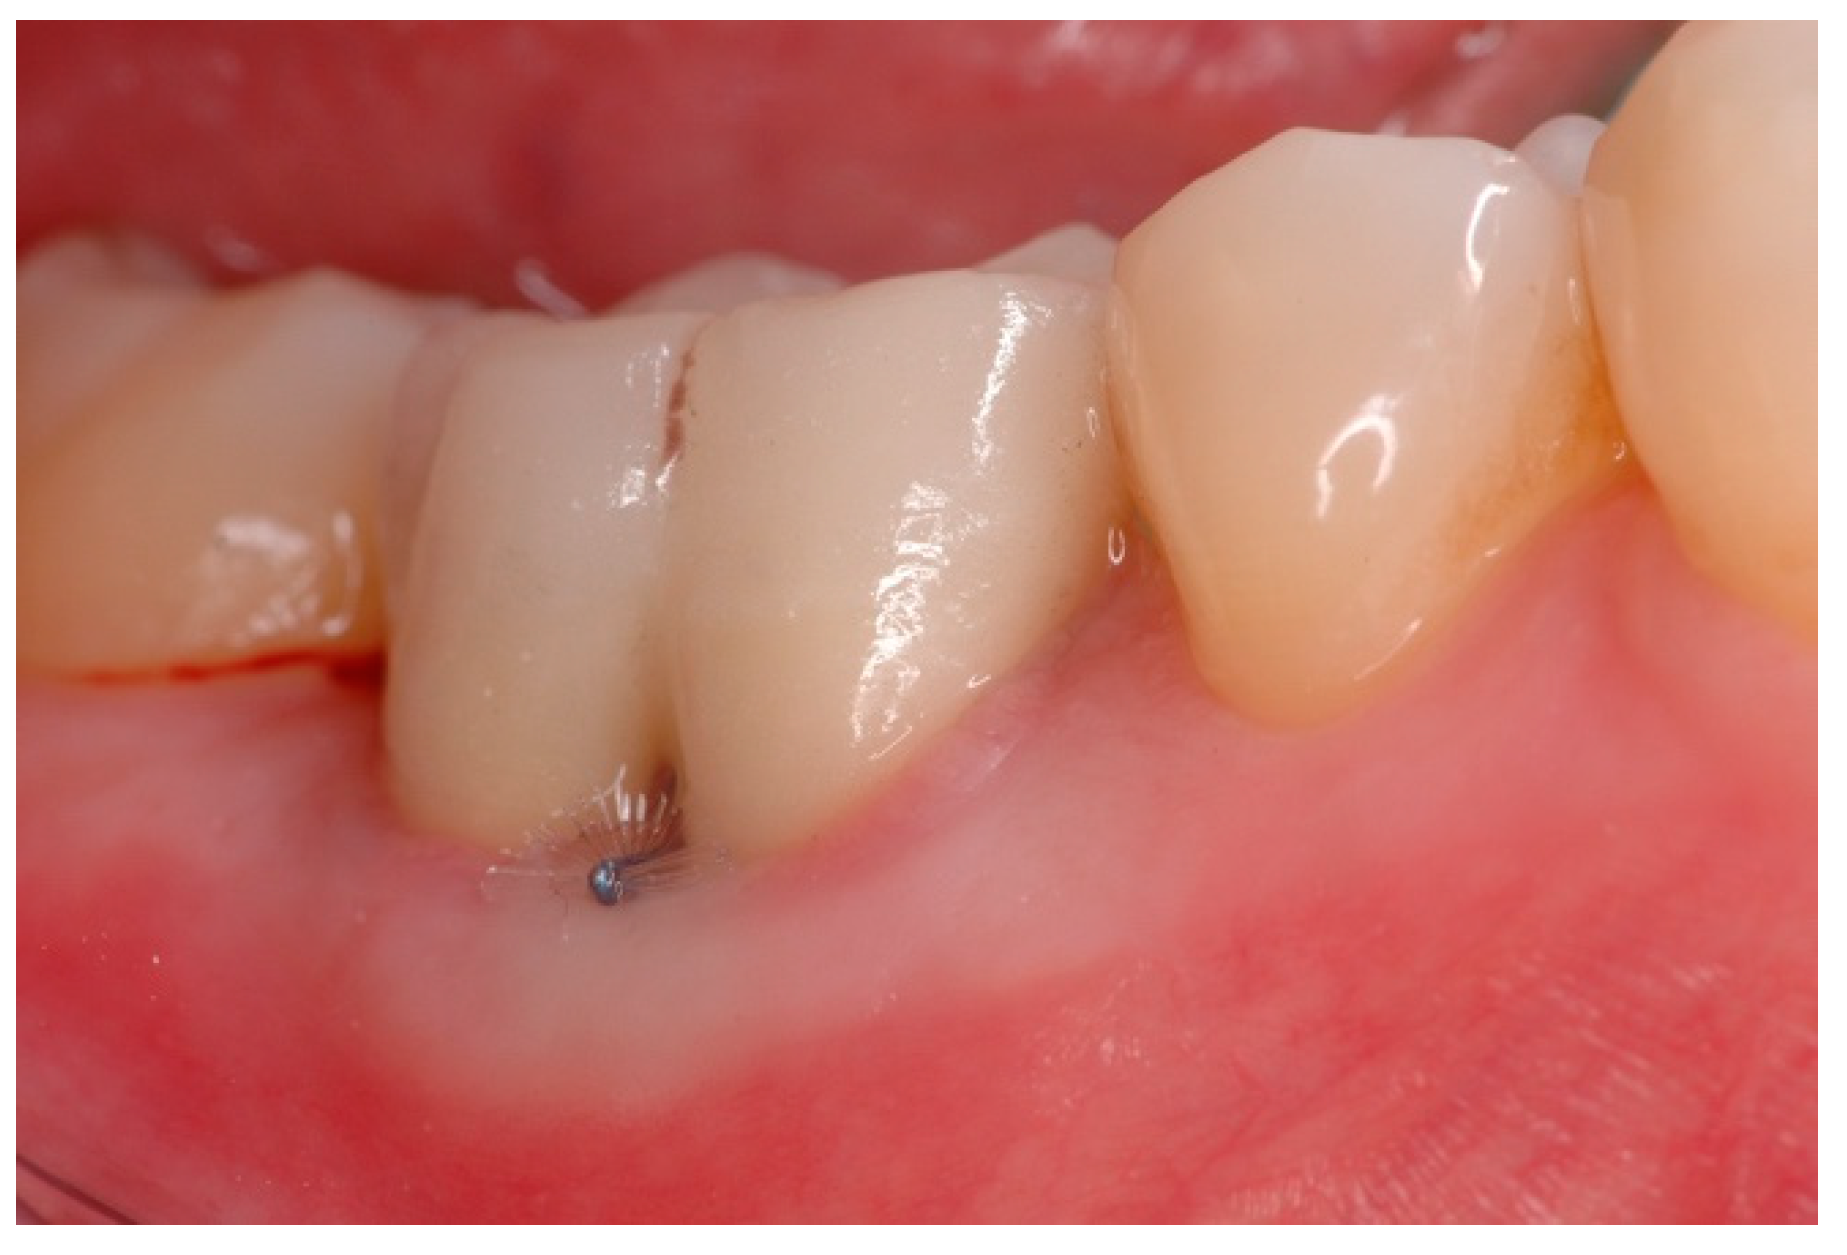

| EI | The furcation lesion is clinically exposed. The horizontal attachment loss is 2 mm or less. |

| EII | The furcation lesion is clinically exposed. The horizontal attachment loss is 3 mm or more. |

| EIII | The furcation lesion is clinically exposed. The horizontal attachment loss is total, with through and through opening of the furcation. |